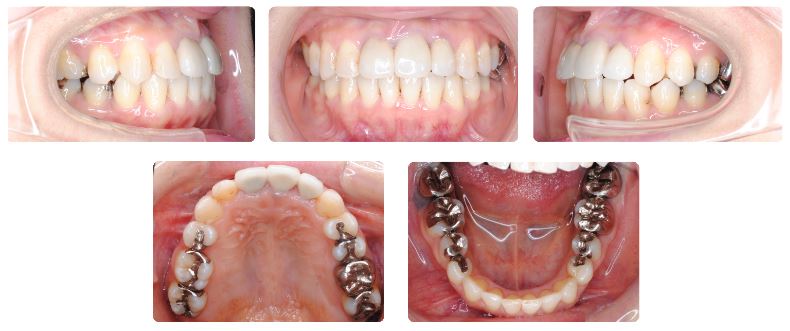

治療期間:2年9ヶ月

治療期間は2年9ヶ月でした。

上あごの矯正治療を先行していますが、前歯だけでなく臼歯の噛み合わせがとても深かったため下あごの歯に装置が装着できるようになるまで時間を要しました。